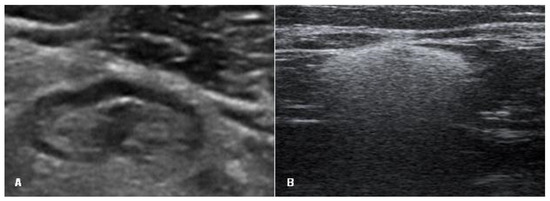

Breast MRI was performed in 17.1% of cases (n = 26). Of them, 14 (53.8%) were intact based on the findings on MRI and confirmed during surgery, while in 46.2% (n = 12), MRI showed a ruptured implant (Figure 4). However, the rupture was confirmed during surgery in 11 cases. One flipped-over but not ruptured implant was detected (Figure 5).

In the case of an intact implant, all three US signs of an intact implant—even implant shell, homogeneous content, and normal axillary lymph nodes—were observed most frequently (93.6%). In the remaining cases, implants had one US sign of a ruptured implant: one implant had an abnormal implant shell, three implants showed inhomogeneous content, and two implants appeared as undamaged, but axillary lymph nodes contained silicone. In the group of ruptured implants, only in one case (1.7%), there was no single sign of rupture on US. ≥2 signs of implant rupture on US were observed in 48 cases (82.8%), and only one sign of implant rupture on US was documented in 9 cases (15.5%), and it was an abnormal implant shell (Figure 6).

Analysis of these results showed that during US examination, only one sign of implant rupture was found in 15 cases: of them, 2 cases had silicone in lymph nodes (the implant itself looked intact), and the remaining 13 cases had only one sign of implant rupture. Of them, only inhomogeneous content was found in 3 cases (the implant was intact in all these cases), and in 10 cases, US showed only abnormal implant shell (on surgery, 9 cases had a ruptured implant, and in 1 case, the implant was not ruptured just flipped over (n = 9, 90% vs. n = 1, 10%)).

Our additional objective was to identify the main signs of an intact and a ruptured breast implant. On US, in the intact implant group, the shell was even and continuous as well as the content was homogeneous statistically more often than in the ruptured implant group (98.9% and 96.8% vs. 1.7% and 17.2%, p < 0.001). If both these signs of the ruptured implant were evident on US, MRI was not performed. In our study, of the 61 ruptured implants diagnosed by US, 48 (78.7%) had ≥2 signs, and the rupture was confirmed during surgery. When only one sonographic sign of a ruptured implant was found (uneven shell or inhomogeneous content), MRI was performed to verify implant integrity. The only sign by US and MRI (abnormal implant shell) was found in 10 cases (nine ruptured implants were confirmed during surgery). One implant with the signs of an abnormal shell was found to be not ruptured, but only flipped over; therefore, it is very important to know the signs of a flipped breast implant to avoid false-positive findings and unnecessary surgery at the same time since usually plastic surgeons can manually manipulate flipped implants into their correct position. The inhomogeneous content alone by US and MRI was found in three cases (surgically all these implants were intact). Silicone implants may also contain impurities, or the silicone gel may begin to aggregate or solidify over time, and these features on US examination may create spurious echoes within the implant and thus mimic implant rupture [22]. Based on these findings, we can conclude that the most important US sign of a ruptured implant is an abnormal implant shell, and in the presence of only inhomogeneous content, women could be followed up with US over time without any urgency of surgery.

Figure 5. Breast implant displacement: signs of the flipped implant on ultrasound. (A,B) Images of the bottom of the same implant (manufacturer Motiva): (A) beginning of the implant bottom and (B) middle of the implant bottom; (C) only the bottom of the other implant (1—an intact shell, white arrows—the implant bottom looks like an abnormal shell: one additional line is seen only in the area of the implant bottom); and (D) natural image of the implant (a black circle indicates the implant bottom).